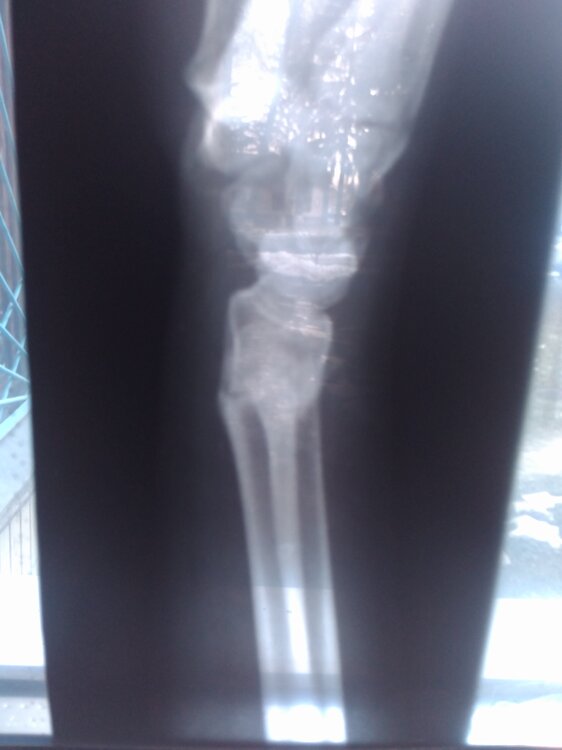

Sumchanka Опубліковано: 4 березня 2018 Автор Поділитись Опубліковано: 4 березня 2018 Хочу рассказать историю, которая сейчас происходит у нас с дочкой. Возможно кто-то для себя вынесет какой-то урок. Итак... Перед Новым годом дочка сломала левую руку в лучевой части перед кистью. Перелом был закрытый со смещением. Упала практически дома-перед калиткой соседей. И потом, толи от болевого шока, толи ещё по какой причине, нам не сказала, а поехала с друзьями в больницу. В трампункте городской больницы вправили, наложили гипс,вернее пародию на гипс-и не гипс и не лангета,ерунда короче... Врача закрепили ещё того ,"умника"- то справку не выпишу, то с кабинета нас выгонял, направление на контрольный снимок не давал-сплошные нервы. И вот, снимают гипс, а рука болит и болит, да плюс с подвижностью что-то не то. Обратились к зав. отделению, сделали снимок-результат: Перелом,который сростается(фото). И это спустя 35 дней... За это время он должен был сростись. И вот этот заведующий нам предлагает походить на процедуры и это при том, что снимок показал отклонение в сростании частей лучевой кости- как потом нам сказали в областной ортопедии-от 15 до 18°. Предложений от врачей городскоц ортопедии исправлять ситуацию не последовало, хотя спрашивала... Тогда подключили знакомых и договорились с одним из лучших ортопедов областной больницы ломать повторно руку, исправлять ось лучевой кости. Оставался вопрос :либо пластина, либо спицы. По ходу подготовки операции и в ходе её решили ставить спицы. И вот опять в гипсе ещё минимум на 1 мес + появился шов... А перед этим дочка делала снимки для заграничного модельного агенства. А теперь контракт под большим вопросом-есть требования по коже и её повреждениям... А ещё вся эта история случилась в разгар сессии-пытаемся хоть как-то закрыть. Да и начался новый семестр-тоже сдавать хватает чего. Несмотря на то ,что рука левая, чертежи и рисунки будущему архитектору делать очень затруднительно. Мораль: - дорогие родители-берите все в свои руки, а дети,даже взрослые-слушайтесь родителей; - без денег тебя зовут никак и ты для всех никто( по ходу лечения в городской больнице дали понять-если бы дочка поступила с родителями и с деньгами, то и гипс был бы другой и отношение...) Берегите себя и своих близких. Своевременная и правильная помощь позволит сьекономить и деньги и нервы . Всем здоровья! 17 Посилання на коментар Поділитися на інших сайтах More sharing options...